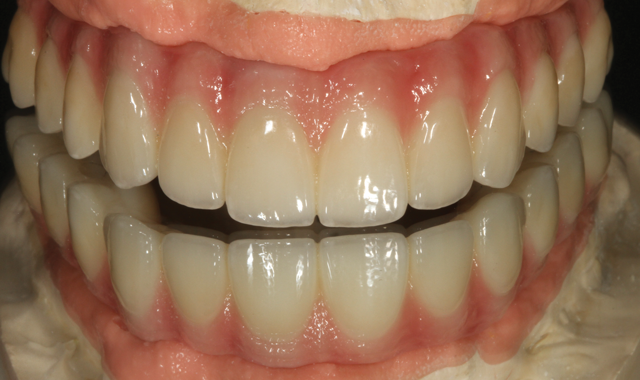

Fig. 11 Mirrored image final restoration

The author utilized and applied an A1 base color for the incisal area, with translucency (Fig. 11).